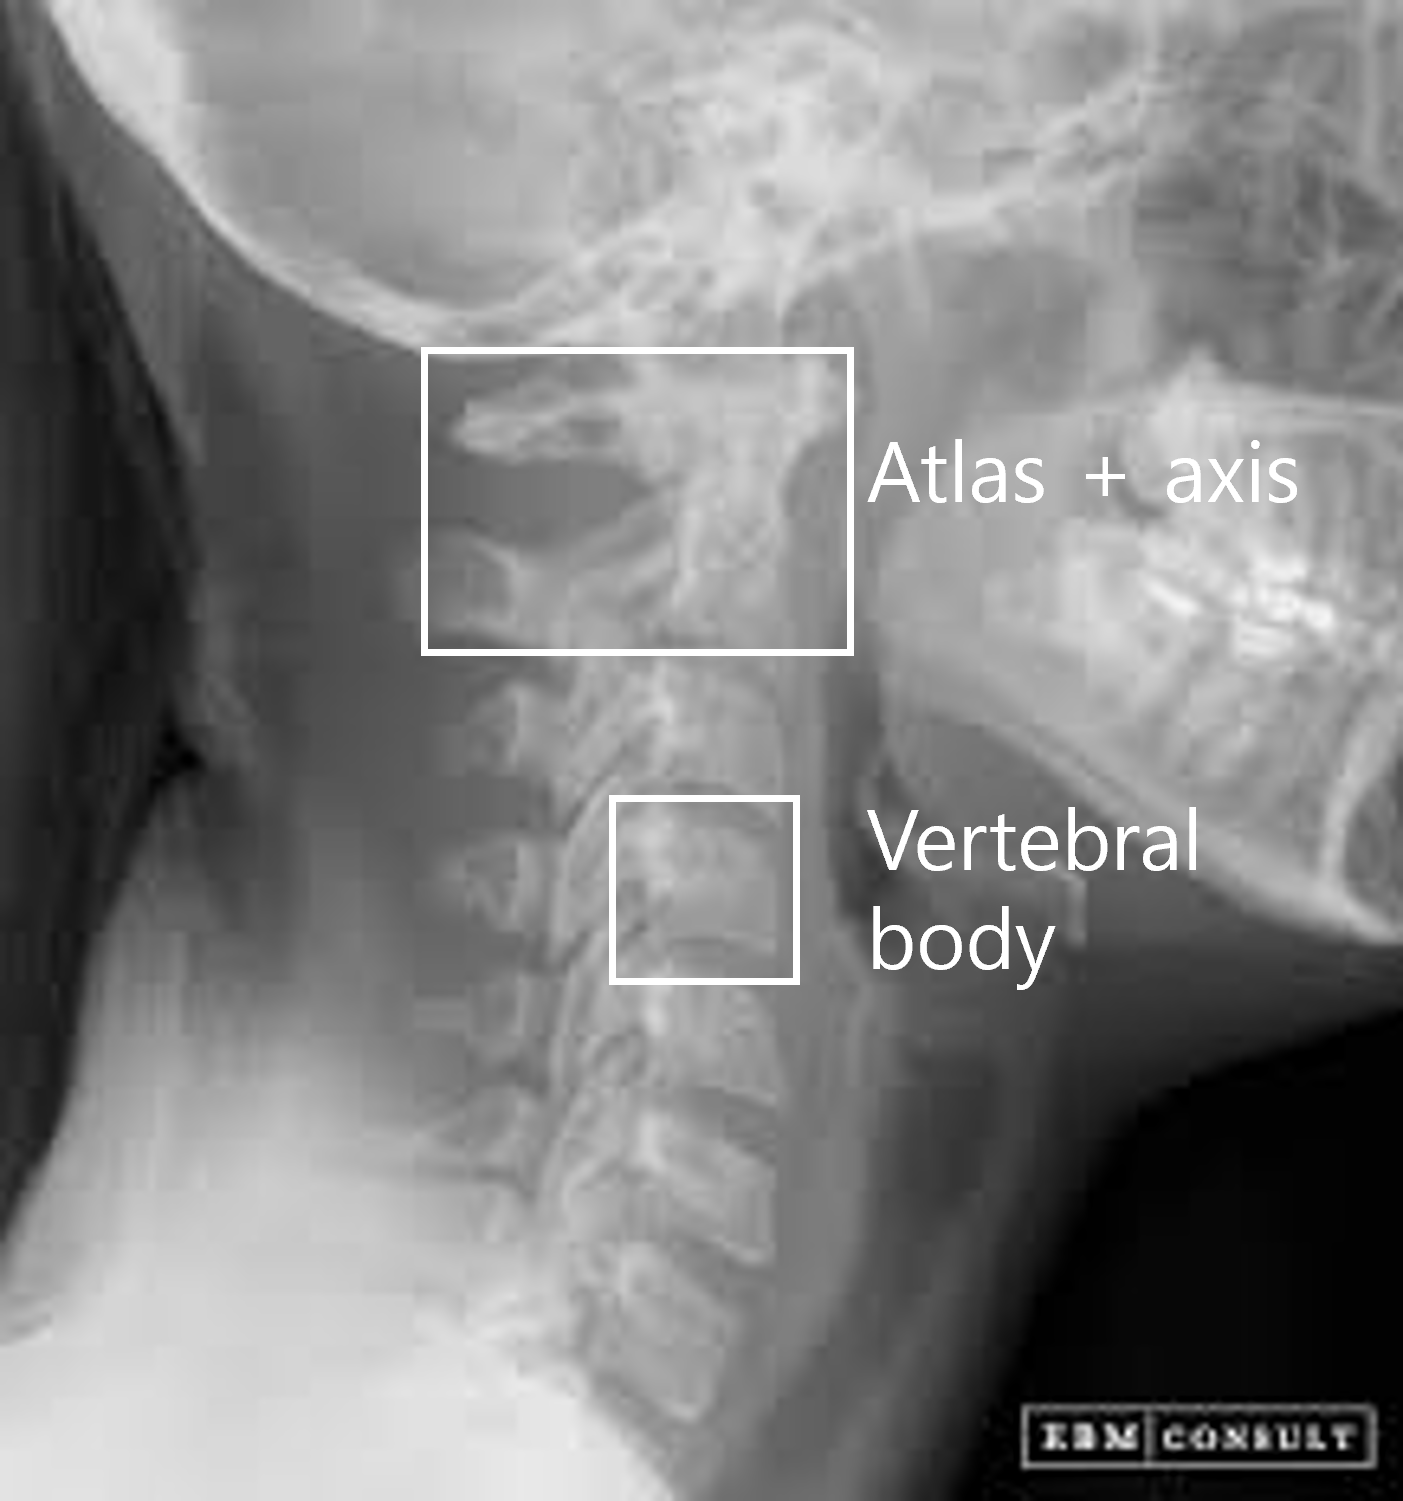

AI 모델이 의료 영상을 효과적으로 학습할 수 있도록, 각 부위와 촬영 방식(AP, Lateral 등)에 맞추어 세그멘테이션(Segmentation), 키포인트(Keypoint), 바운딩 박스(Bounding box) 등 세 가지 방식의 정밀 라벨링 작업을 복합적으로 수행했습니다.